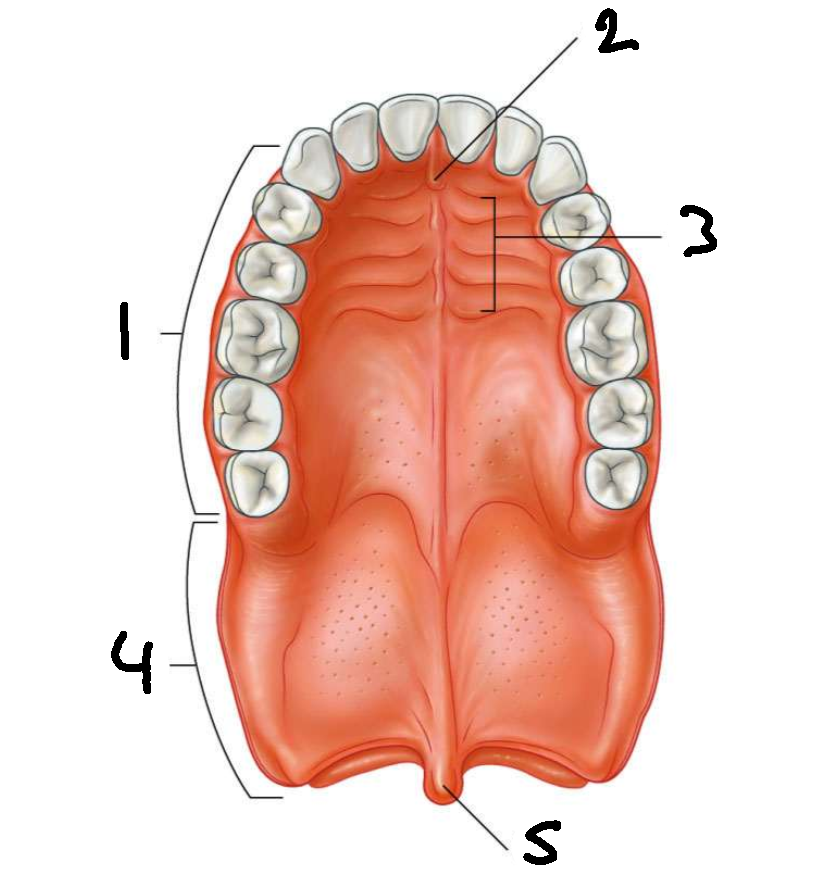

What is 1?

hard palate

What is 2?

incisive papilla

What is 3?

palatine rugae

What is 4?

soft palate

What is 5?

uvula